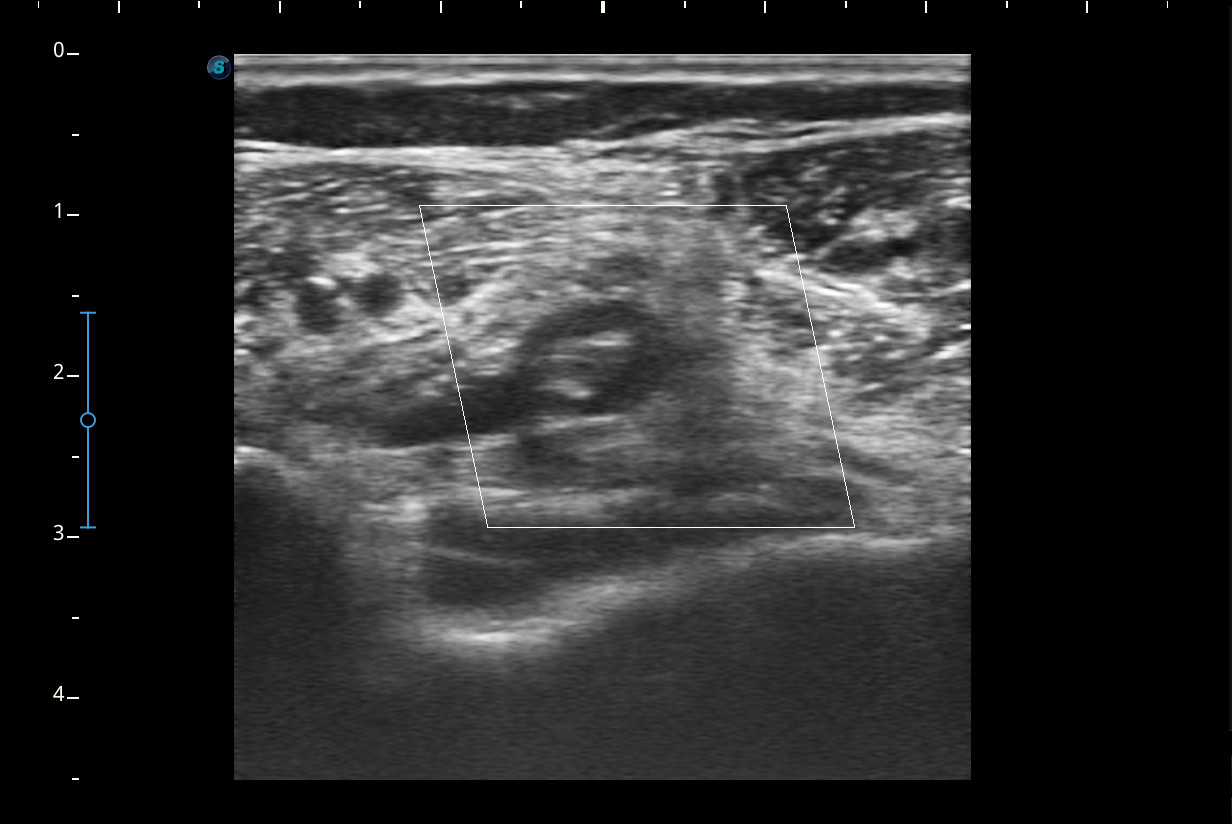

Se realiza ecografía del Miembro inferior derecho.

A nivel del hueco poplíteo se visualiza presencia de trombosis de la vena poplítea, no así en localizaciones proximales.